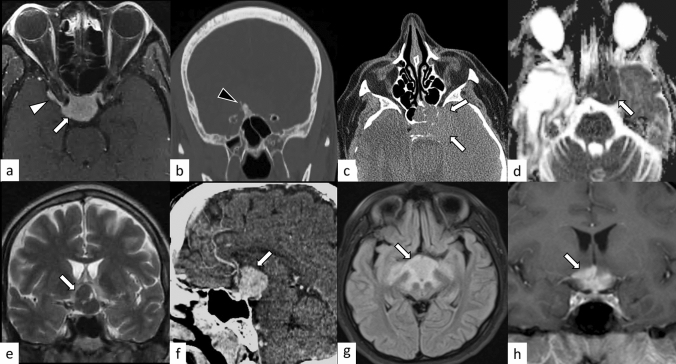

Fig. 16.

a, b A 49-year-old man with meningioma. Post-contrast fat-suppressed T1-weighted image shows homogeneously enhanced suprasellar mass (a, arrow). Dural-tail sign (a, white arrowhead) and hyperostosis (b, black arrowhead) are observed. c, d A 60-year-old woman with lymphoma. Non-enhanced CT shows an infiltrative hyperdense suprasellar mass (c, arrowheads), which shows restricted diffusion with low apparent diffusion coefficient (d, arrow). e, f A 51-year-old man with pituicytoma. T2-weighted coronal image shows a suprasellar well-defined mass with homogeneous hypointensity and small cystic areas (e, arrow). Contrast-enhanced CT shows homogeneous enhancement (f, arrow). g, h A 14-year-old girl with Rosai–Dorfman disease. FLAIR image shows an infiltrative suprasellar mass with an ill-defined margin, involving the midbrain and bilateral thalami (g, arrow). Post-contrast T1-weighted image shows heterogeneous and strong enhancement (h, arrow)

Fig. 17.

A 53-year-old woman with sarcoidosis. Enlarged pituitary gland and stalk with homogeneous and strong contrast enhancement are observed (a–c, white arrows). The posterior pituitary T1-weighted bright spot is absent (a, black arrow). The lesion is extending into the bilateral cavernous sinus (c, white arrowheads). Chest CT shows mediastinal lymphadenopathy, highly suggestive of sarcoidosis (d, black arrowheads)

Fig. 18.

A 20-year-old man with proteinase 3-antineutrophil cytoplasmic antibody-positive GPA. The pituitary gland is enlarged and shows heterogeneously hypointensity on T2-weighted coronal image (a, white arrow) with heterogeneous enhancement (b, white arrow), extending posteriorly along the surface of the clivus (b, white arrowhead). The sphenoid sinus (b, black arrow), bilateral lacrimal glands (c, black arrows), right mastoiditis (d, black arrow), and left lung (e, black arrow) are also involved